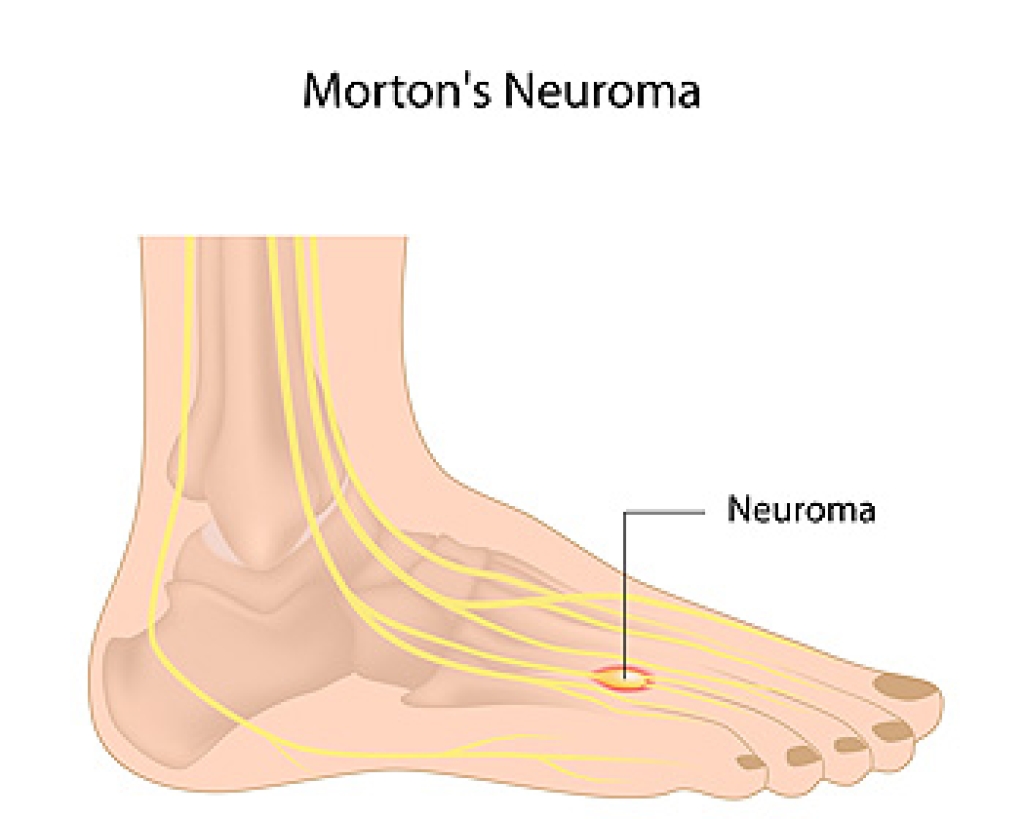

Charcot-Marie-Tooth disease is a cluster of inherited genetic disorders that impact the peripheral nervous system. These neuropathies disrupt the intricate network responsible for movement and sensation within the extremities, including the feet. The peripheral nervous system serves as a communication bridge between the brain, spinal cord, and muscles. Charcot-Marie-Tooth disease results in a range of symptoms that interfere with this process and dramatically influence foot health. Gradual muscle wasting in the feet and legs is a hallmark of this disease, causing increasing weakness and reduced control over time. This frequently leads to difficulties in mobility and balance. It also can result in high foot arches, known as pes cavus, and clawed toes. These structural changes can further impede proper foot function and comfort. An altered gait, often high-stepping, and a slapping sound when walking are only some of the common symptoms. Poor balance and a risk of falling are others, caused by weakened muscles and loss of sensation. Although there is no cure, it is possible to manage foot-related challenges and potentially slow down the progression of the disease. For guidance, it is suggested that you make an appointment with a podiatrist.

Systemic diseases affect the whole body, and symptoms usually are displayed in the feet. This condition can make a patient’s ability to walk unbearable. Systemic diseases include gout, diabetes mellitus, neurological disorders, and arthritis.

Diabetic Neuropathy – may lead to damaged nerves and affect the feet through numbness and loss of sensation.